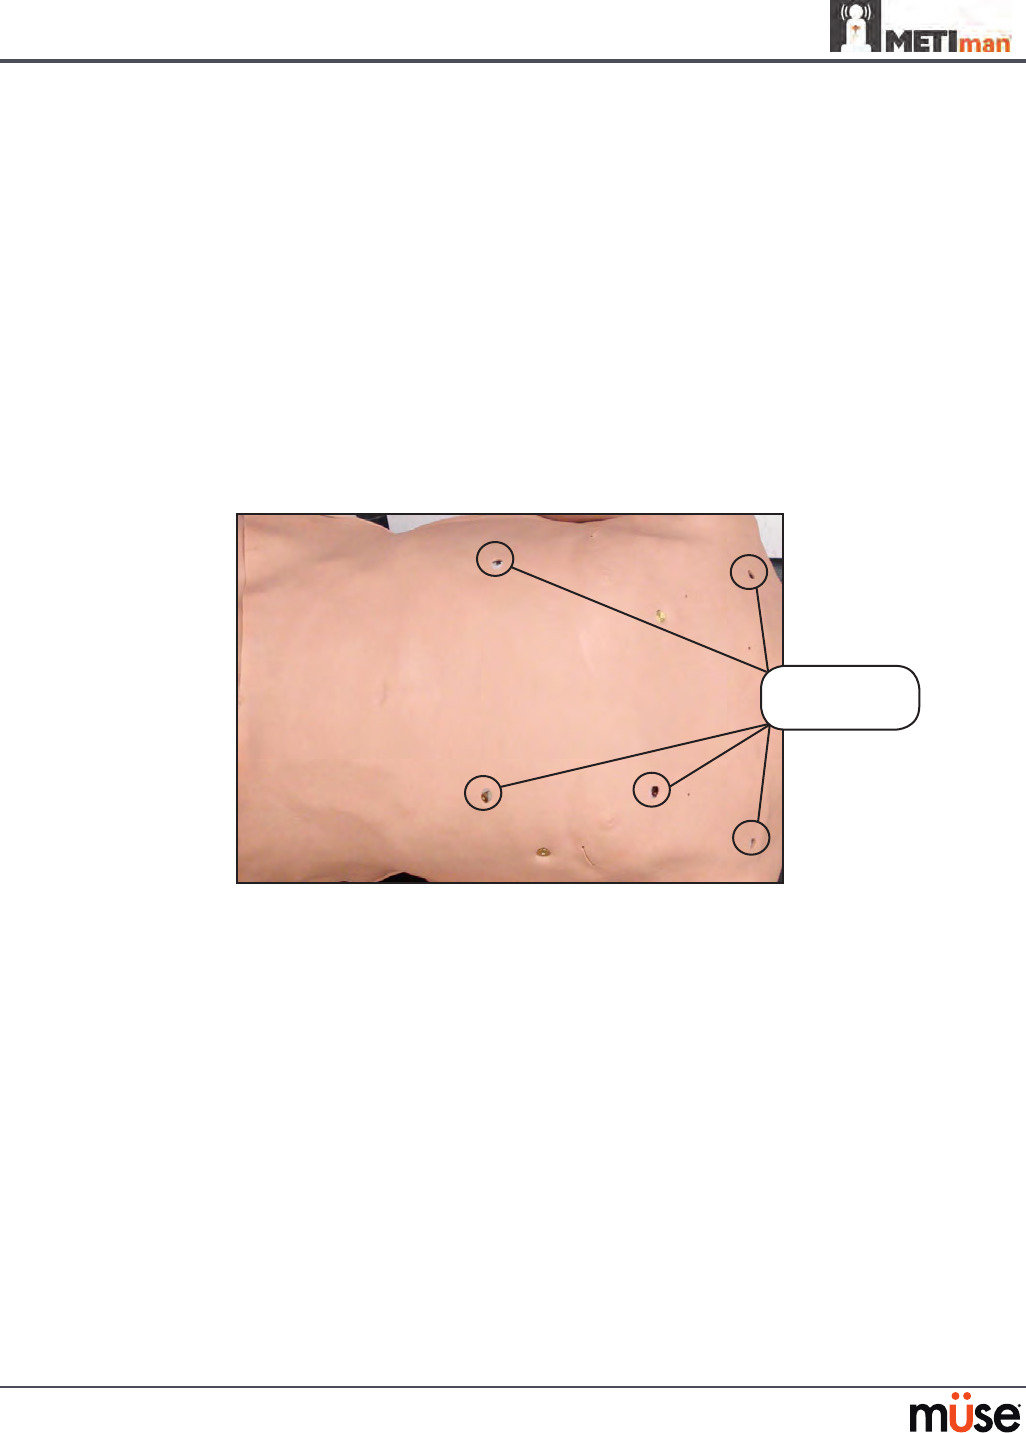

Five-Lead ECG

On METIman, a 5-lead ECG is emitted from the appropriate positions for display on a standard

monitor. A contact is available on METIman’s chest for each of the ve cables.

5-Lead ECG Sites

The simulator generates a normal sinus ECG, as well as a broad range of abnormalities such as

myocardial ischemia, sinus tachycardia and bradycardia, ventricular brillation and asystole.

The hemodynamic response to the arrhythmias is physiologically correct. Myocardial oxygen

balance and cardiac ischemia automatically inuence the cardiac rhythm resulting in a

realistic and automatic response of the rhythm to hypoxemia. The degree of inuence can be

controlled or completely overridden by the instructor.

Five-Lead

ECG sites